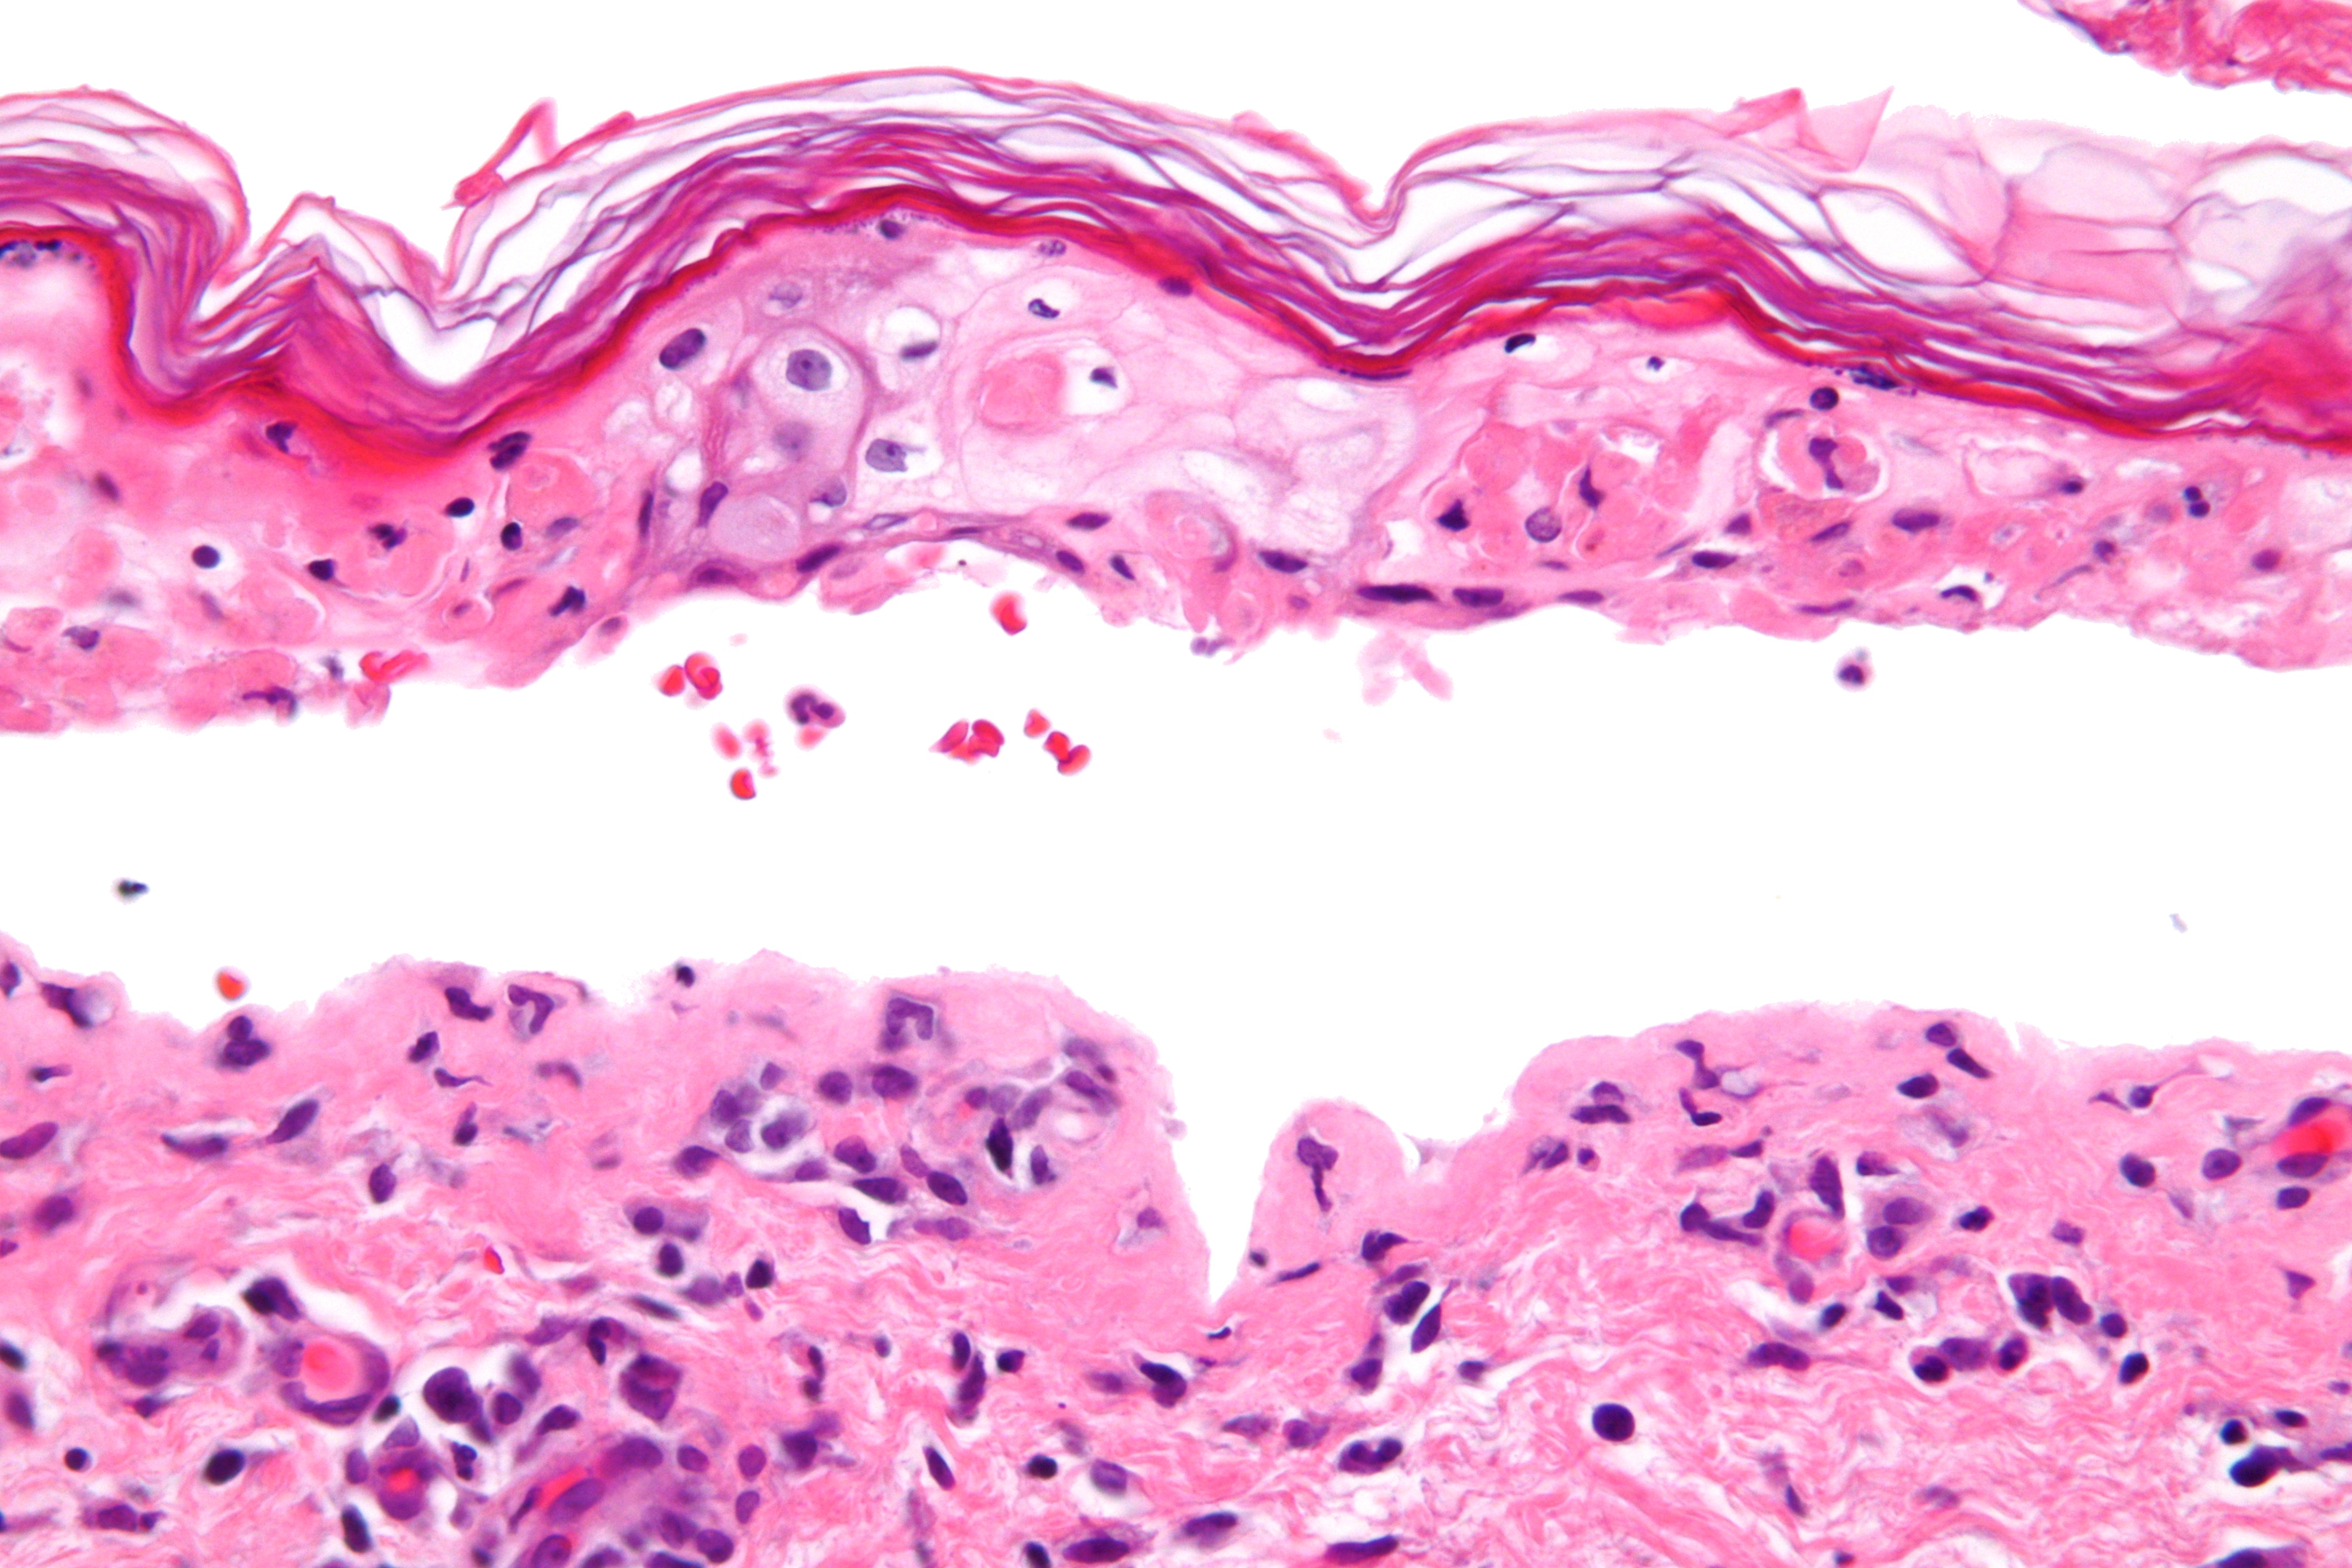

SJS는 TEN 및 다형 홍반과 마찬가지로 관련 염증이 최소화된 융합된 표피 괴사가 특징이다. 급성도는 각질층의 (정상적인) 바구니 짜임 패턴에서 분명하게 나타난다.

증상 및 징후만으로는 SJS(스티븐스-존슨 증후군)와 다형 홍반(EM Major)을 구별하기 어렵지만, 피부 생검을 실시하면 표피 세포가 괴사·용해되어 다형 홍반과의 감별이 가능하다.[68]